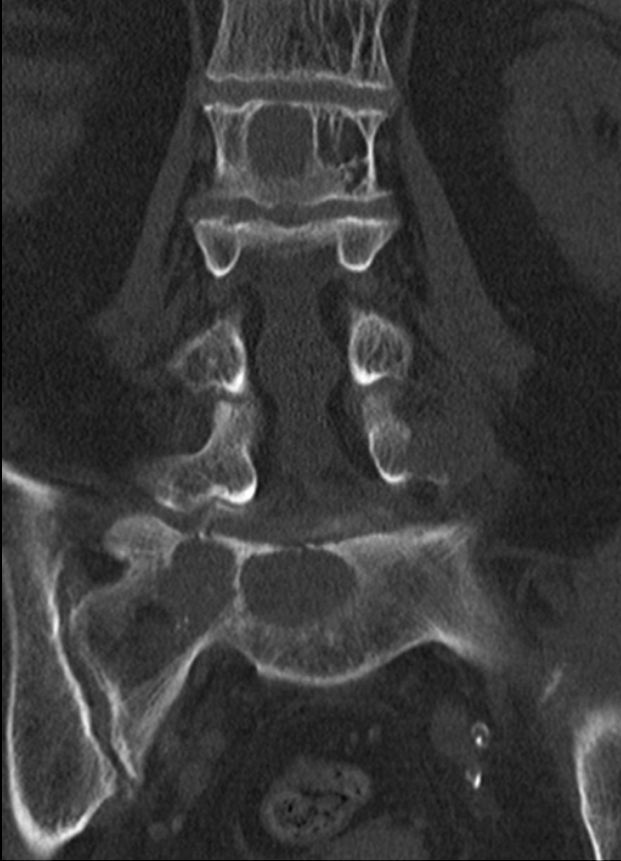

82-jährige Frau mit einem Leiomyosarkom der Vulva rechts pT2a N0 M0, V1, G2.

Klinik: Vulva-Tumor rechts. Der Tumor ist relativ glatt begrenzt und gut 5 cm groß; er ist auf dem absteigenden Schambeinast beweglich und reicht dicht bis an die Urethralöffnung heran.

8 Monate nach Primärtherapie auftreten von Knochenmetastasen. Kein lokales Rezidiv.